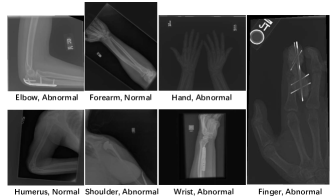

Refer to caption

Figure 2: Samples from MURA dataset. We show X-Rays of seven different parts from human body.

MURA is a dataset of musculoskeletal radiographs, which contains 40,561 images from 14,863 patient studies. X-Ray images are collected from seven parts of human body: elbow, finger, forearm, hand, humerus, shoulder and wrist (cf. Figure 2). The goal of this dataset is to distinguish normal musculoskeletal studies from abnormal ones (a study often contains more than one image). In this paper, we make a modification to this goal: to simply tell the difference between normal and abnormal radiographs (one image). The reason why we’d like to evaluate SSL on MURA is that we hope to check the value of SSL when ImageNet pre-trained models are not that useful.